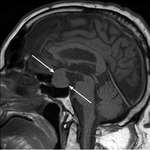

Guz przysadki

Z uwagi na lokalizację wewnątrzczaszkową w pobliżu skrzyżowania nerwów wzrokowych guzy przysadki (zwłaszcza makrogruczolaki) objawiają się bólami głowy i zaburzeniami widzenia w postaci pogorszenia ostrości widzenia i ograniczenia pola widzenia (głównie niedowidzenie połowicze dwuskroniowe). Rycina 1 przedstawia MR u pacjenta z makrogruczolakiem przysadki. Objawy miejscowe dominują u chorych z nieczynnymi hormonalnie gruczolakami przysadki, podczas gdy w przypadku guzów hormonalnie czynnych często wyprzedzają je objawy związane z nadprodukcją hormonalną. Do najczęściej występujących guzów hormonalnie czynnych należą: guzy wydzielające prolaktynę, hormon wzrostu (GH – growth hormone) lub adrenokortykotropinę (ACTH – adrenocorticotropic hormone).